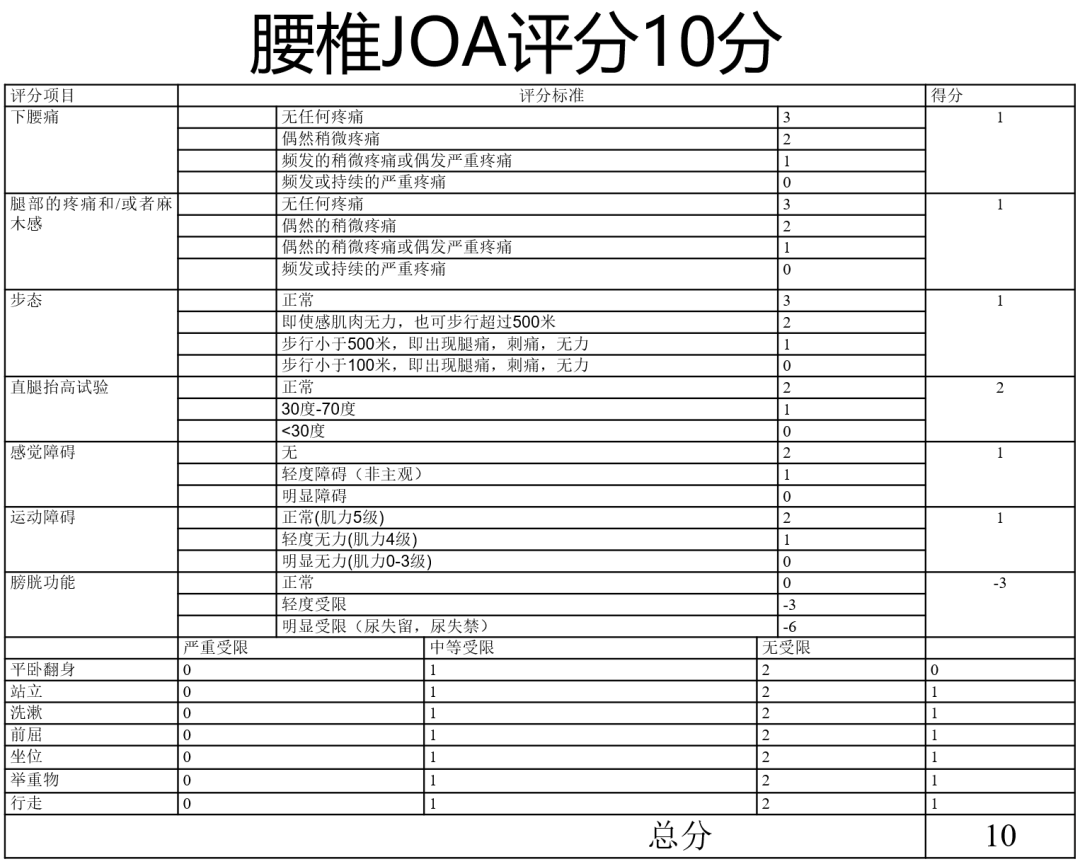

腰背痛2年,加重伴腰部后凸不能直立半年

Diagnosis:

腰椎侧后凸畸形

腰椎陈旧性压缩性骨折(L4)